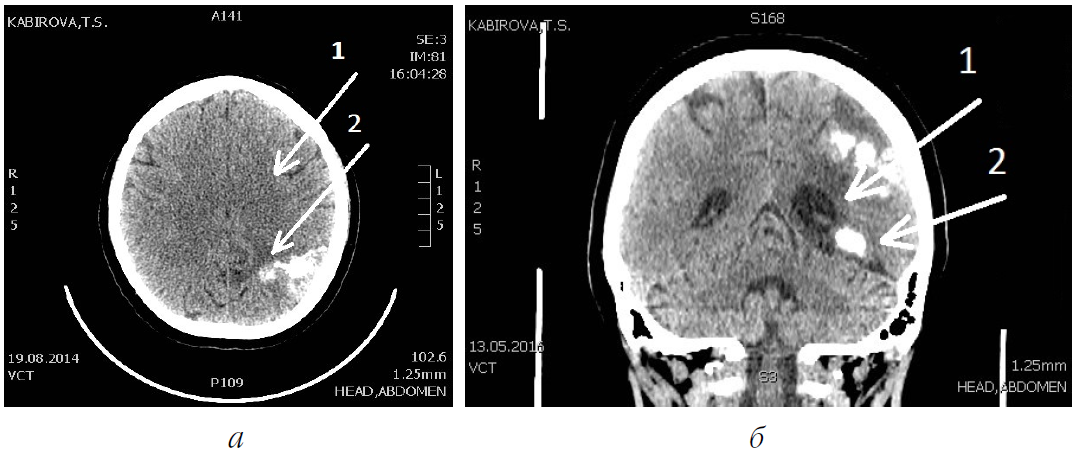

При контрольном исследовании головного мозга на компьютерной томографии от августа 2014 г. отмечено: «...в левом полушарии головного мозга имеются ... множественные участки повышенной плотности неправильной формы с наличием петрификатов ... Заключение: патологические изменения в виде эхинококковых кист ...» (рис. 2).

Рис. 2. Компьютерная томография головного мозга пациентки К.: а – в аксиальной проекции; б – во фронтальной проекции; 1 – левое полушарие головного мозга; 2 – множественные петрификаты в эхинококковых узлах